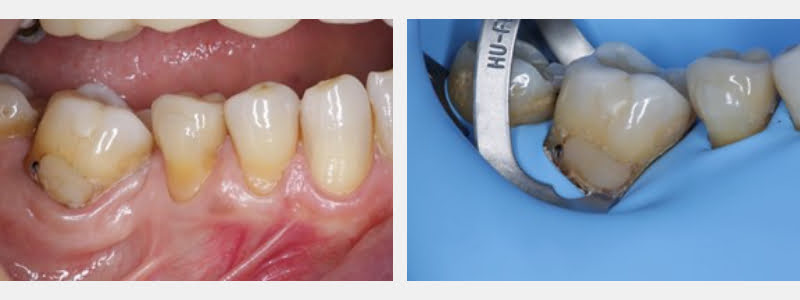

In the following steps, a modified 212 clamp was used to treat a partially edentulous 67-year-old patient, who presented evident signs of parafunction and needed cervical restorations.

- Cervical carious and NCCL were identified on teeth #31, #29, and #28.

- Selected composite resin color before applying anesthesia.

- Administered anesthesia on the patient to isolate the operative field with a W3 clamp placed on the third molar. This widened the field of operatory visibility and maximized tissue retraction and facilitated the use of the modified 212 clamp.

- Performed an absolute isolation technique using a thick rubber dam lubricated with petroleum jelly on the shiny side to optimize tissue retraction on interproximal areas.